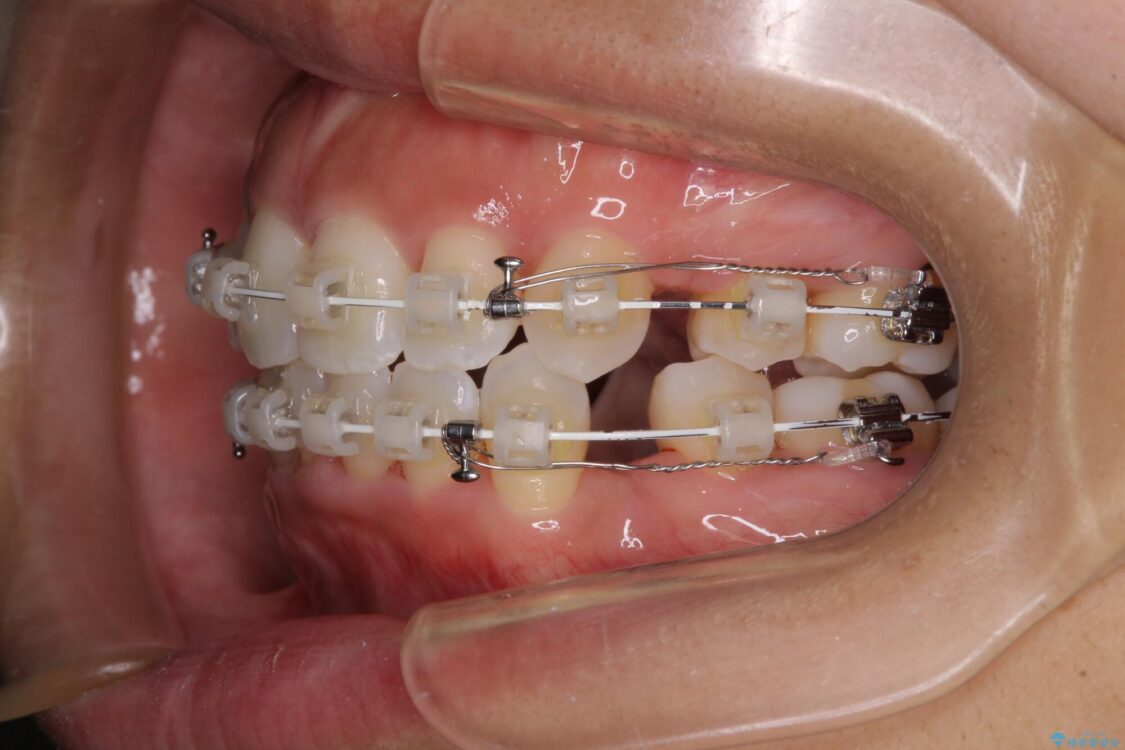

治療途中

• 抜歯矯正で唇を閉じやすく 目立たないワイヤー装置 治療途中画像